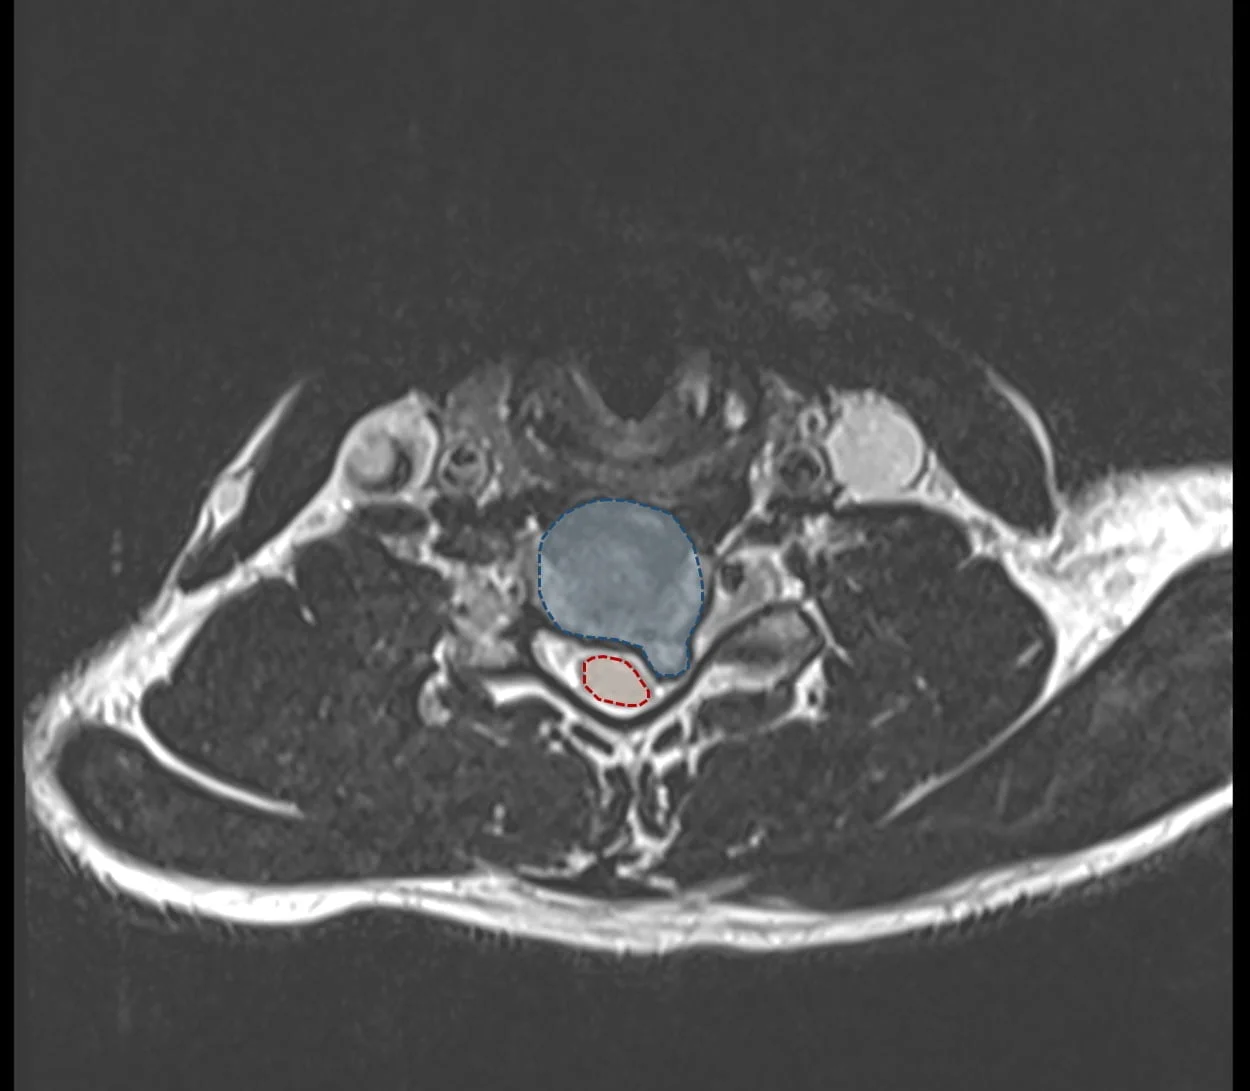

Au milieu : IRM cervicale en coupe axiale montrant une hernie discale cervicale (en bleu) déplaçant la moelle épinière (en rouge).

Le diagnostic de hernie discale cervicale se fait habituellement sur l’IRM cervicale. La hernie apparaît alors comme une excroissance du disque venant comprimer la racine. L’IRM peut évaluer la taille et le retentissement de la hernie, sur les nerfs mais également sur la moelle épinière.